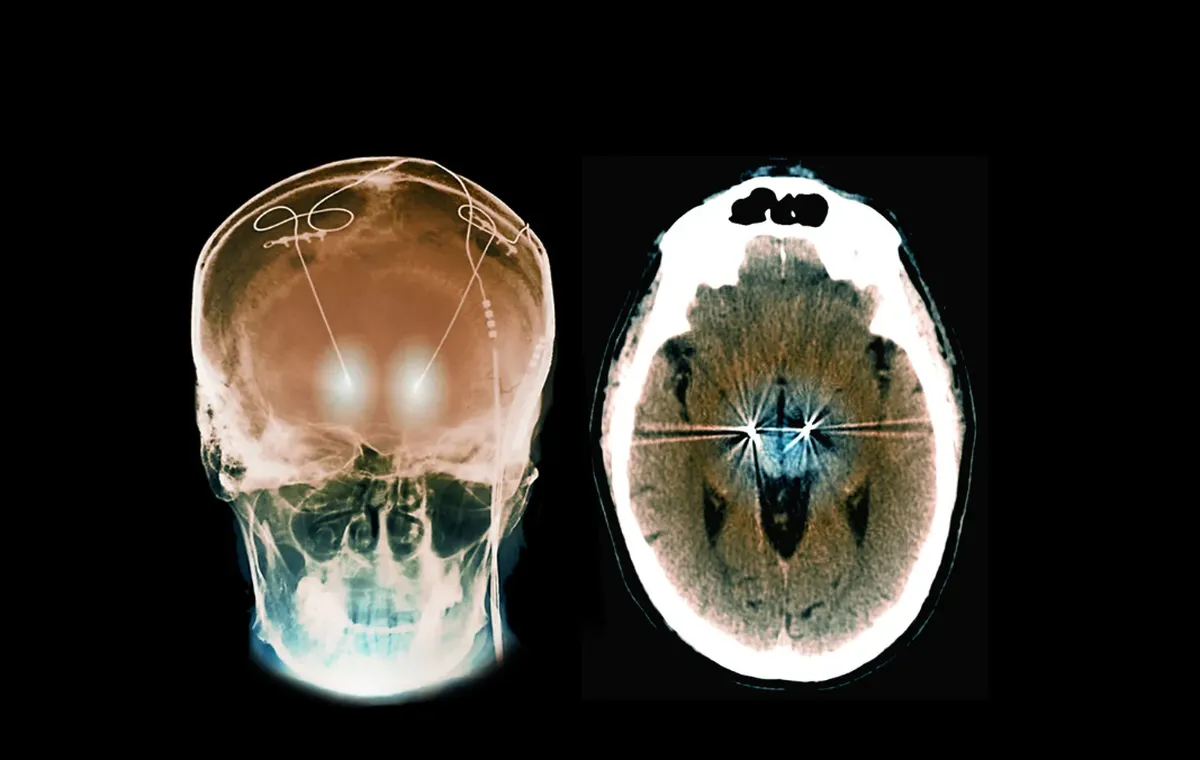

در مطالعهای، تیم پزشکی آمبر گزارش داد که یک الکترود ۳۲ میلیمتری که برای شناسایی سیگنالهای عصبی منحصربهفرد مغز او تنظیم شده بود، توانست هر دو بیماری را کنترل کند. برخلاف DBS سنتی که تحریک دائمی ارائه میدهد، دستگاه آمبر پاسخگو است و فقط وقتی الگوهای نامنظم مغزی که نشاندهنده شروع تشنج یا افکار وسواسی هستند را شناسایی کند، ضرباتی الکتریکی میفرستد.

تشخیصهای آمبر در قسمتی از مغز به نام اینسولا (insula) رخ میداد. جراح اعصاب او، احمد رسولان، تصمیم گرفت ناحیه کوچکی از این قسمت را برای درمان صرع هدف بگیرد و همچنین بخش ونتال استریاتوم (ventral striatum) را که درست بالاتر و پشت چشمها قرار دارد. این بخش شامل هسته «آکومبنس» است که به انگیزه و عمل از جمله تحریکهای اجباری مرتبط است. رسولان میگوید: «این ناحیه را میشد با همان الکترود هدف قرار داد.»

تیم پزشکی از دستگاهی ساخت شرکت NeuroPace مستقر در کالیفرنیا استفاده کرد. برخلاف الکترودهای سنتی DBS که فقط پالسهای الکتریکی میفرستند، این دستگاه هم سیگنالهای مغزی را جمعآوری میکند و هم فقط وقتی تحریک میدهد که یک محرک خاص را شناسایی کند.